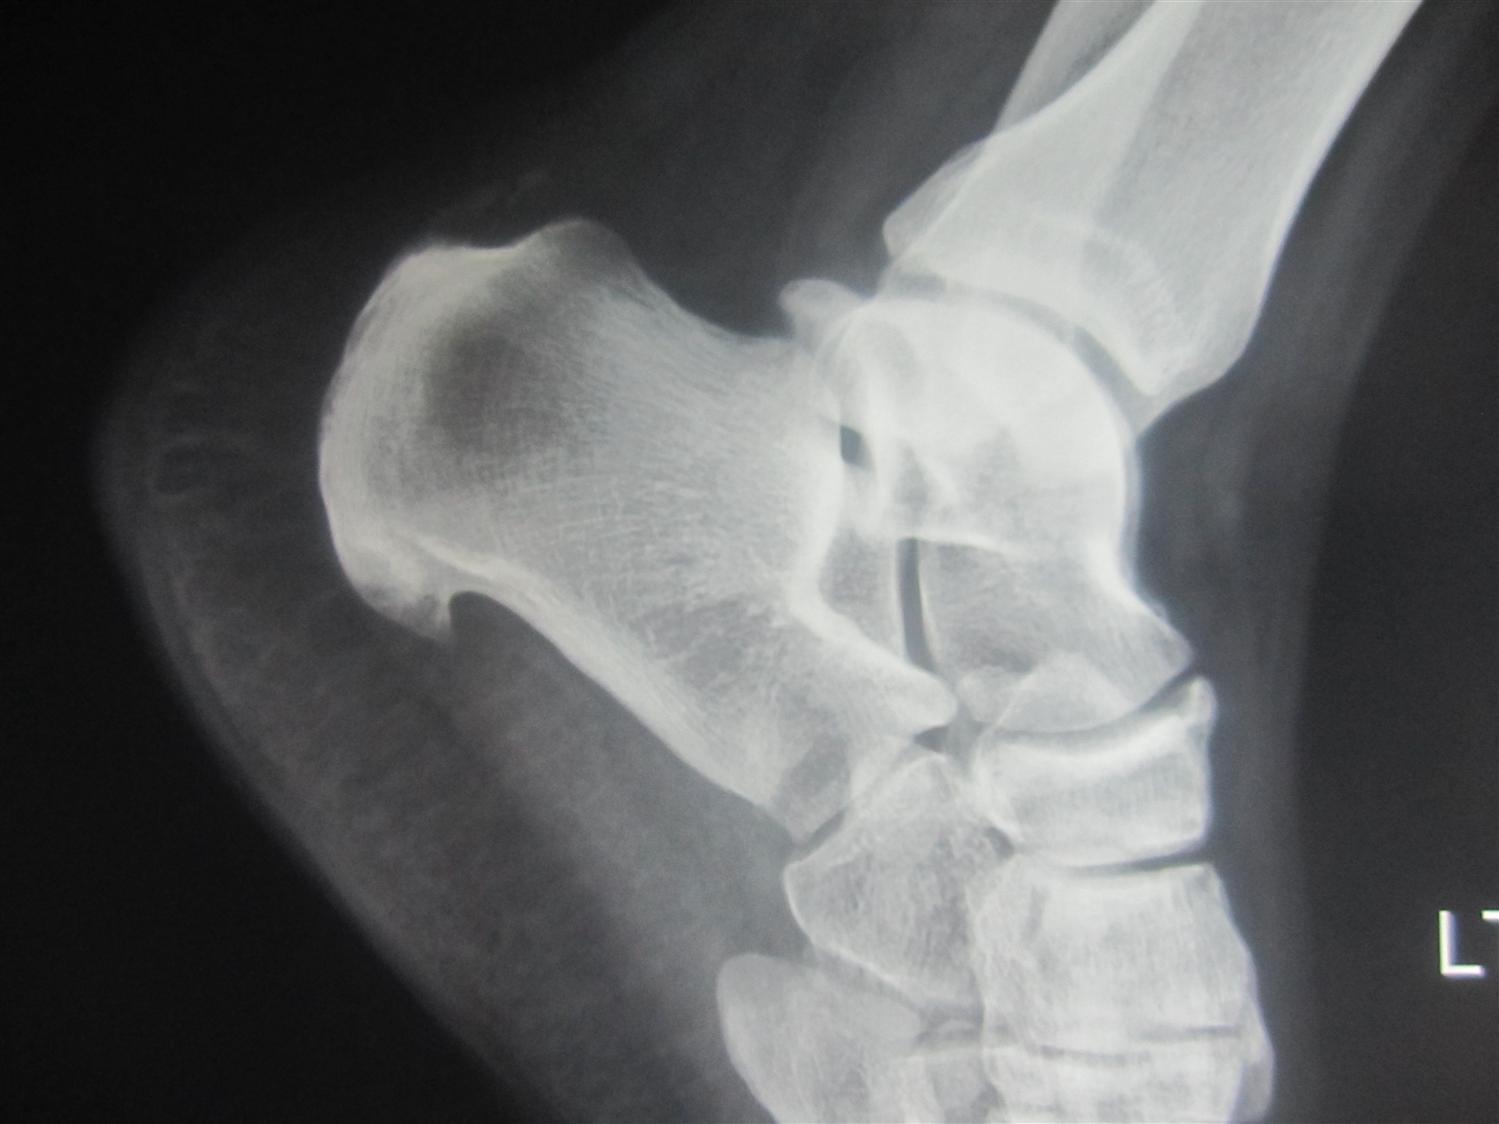

Orthobullets on Twitter "Subtalar arthritis is a common complication Foot Arthritis Orthobullets It can make it difficult to walk and even stand without pain. It occurs when the band of tissue that supports the arch of your foot becomes. midfoot arthritis is defined as arthritis of the midfoot which includes the following joints: hallux rigidus is a common foot condition characterized by pain and loss of motion of the 1st. Foot Arthritis Orthobullets.